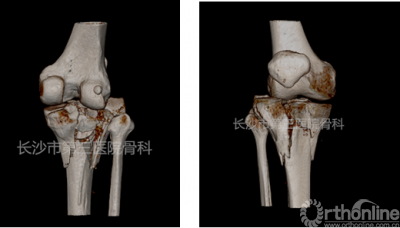

术前CT

从CT三维重建可见骨折累及胫骨平台三柱且粉碎程度十分严重,常规手术治疗往往需要三块钢板分别固定内、外、后三柱,但存在手术切口大,软组织剥离范围广,组织血运影响大甚至出现皮肤软组织坏死等风险。